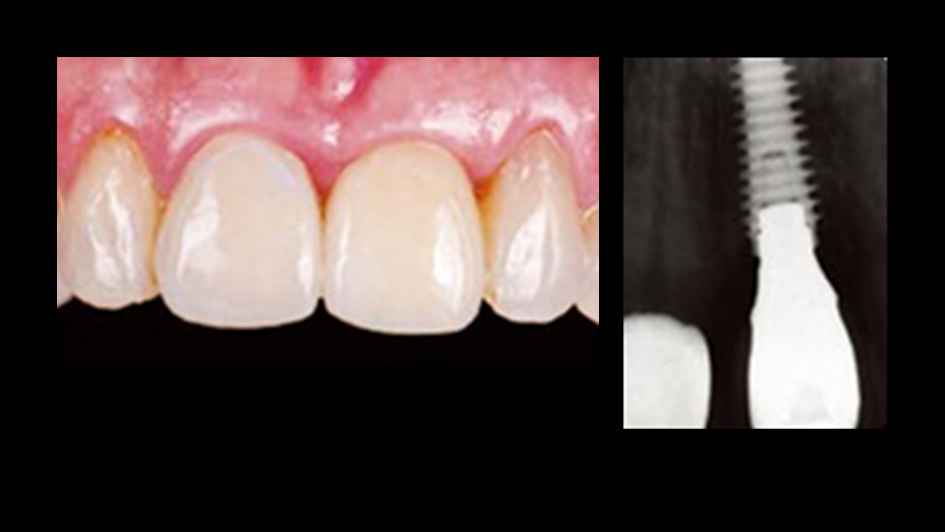

“AnyRidge with Root Membrane Technique shows

comparable long-term success rates to

conventional immediate implants. ”

Clinical case: Replacement of fractured central incisor (#11) with immediate implant

& Root Membrane Technique

- Courtesy of Dr. Miltiadis Mitsias, Greece -

AnyRidge, Root Membrane Technique, retrospective study, long-term study, immediate implants, bone resorption, bone preservation, Dr. Miltiadis Mitsias,survival, success, maxillary anterior, single replacement

AnyRidge implant system, Root Membrane kit

Reference

The Root Membrane Technique: A retrospective clinical study with up to 10 years of follow-up./Implant Dent. 2018 Oct;27(5):564-574

https://www.ncbi.nlm.nih.gov/pubmed/30161062